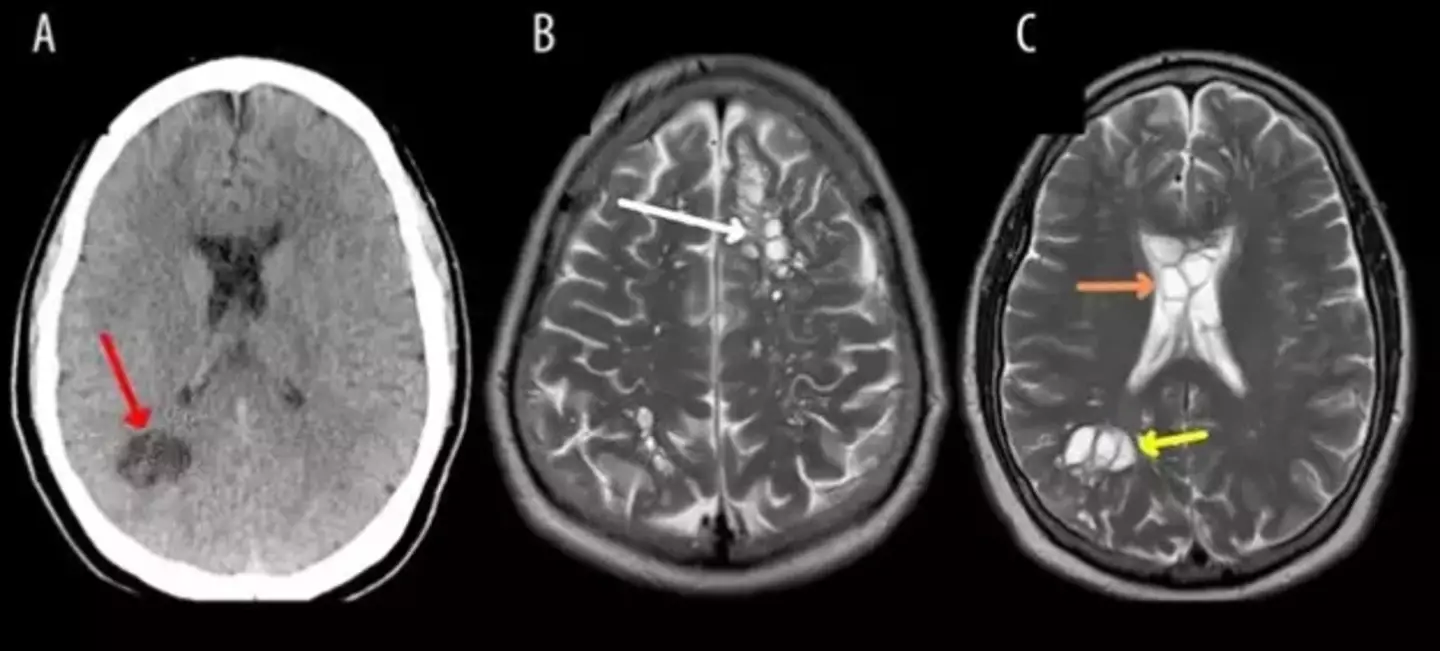

He was given a CT scan, and it revealed the root of the problem.

He was playing host to a set of larval tapeworm cysts in his brain – a condition called cysticercosis that can result from developing an intestinal tapeworm via infected and undercooked pork.

Doctors theorised that he had contracted the cysts via “improper handwashing”, with the initial tapeworm getting into his system through undercooked bacon.

He was initially discharged after two weeks, with a “regression” in brain lesions and improvements to his headaches.